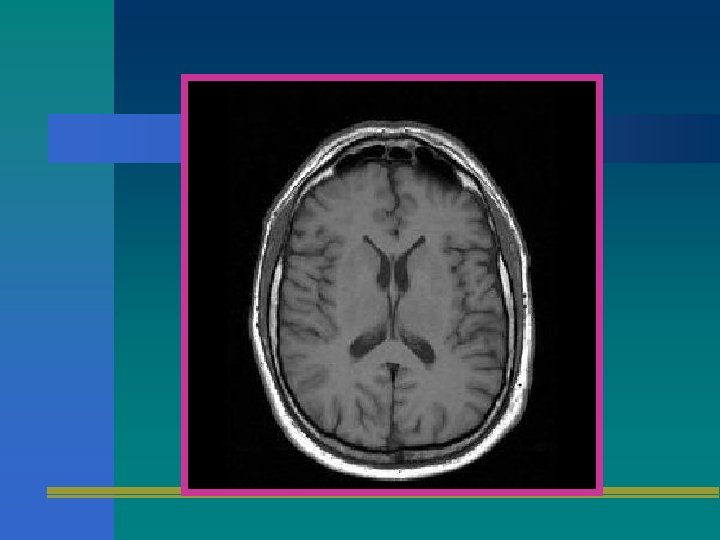

SECUENCIA T 1 • UTILIZA UN ECO GRADIENTE CON TR CORTO Y TE CORTO. • ES EL ESTUDIO DE RMN BASICO. • ES EXCELENTE PARA RECONSTRUCCIONES EN 3 D. • ES EXCELENTE PARA VISUALIZACION ANATOMICA. • PROVEE EXCELENTE CONTRASTE DE SUSTANCIA GRIS Y BLANCA.